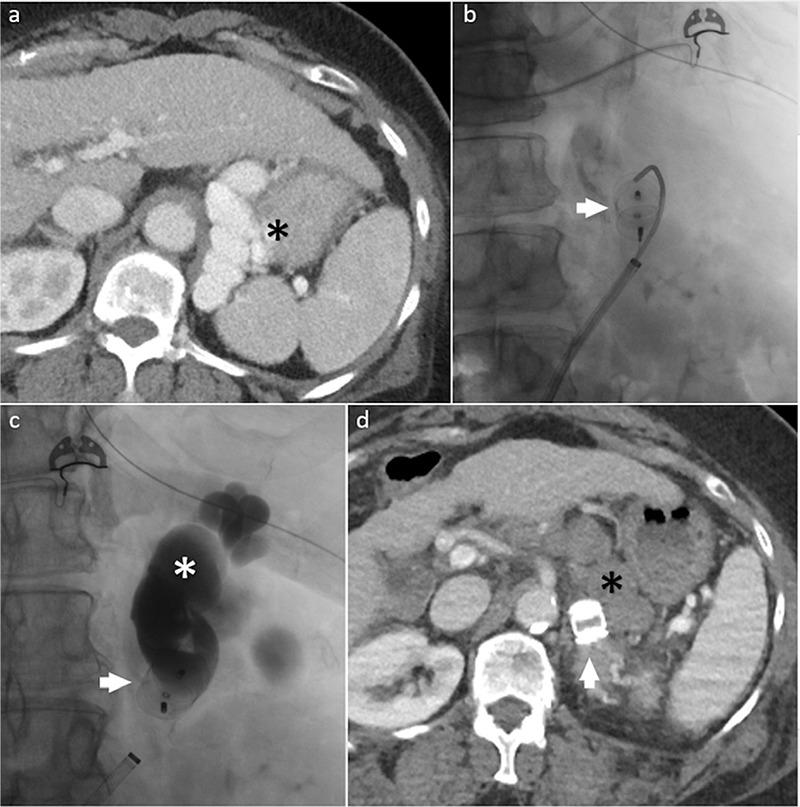

Bleeding gastric varices (GVs) is a life-threatening complication of portal hypertension, with higher morbidity and mortality rates compared with bleeding esophageal varices (EVs). The endovascular techniques for the management of GVs are mainly transjugular intrahepatic portosystemic shunt (TIPS) and transvenous obliteration of the GVs. Transvenous obliteration techniques can be an alternative or an adjunct to TIPS for treatment of GVs, depending on the clinical scenario, and are less invasive than TIPS. However, these procedures are associated with increased portal pressure and related complications, mainly worsening of the EVs. In this article, the different techniques of transvenous obliteration of GVs, their indications, contraindications, and outcomes are discussed.